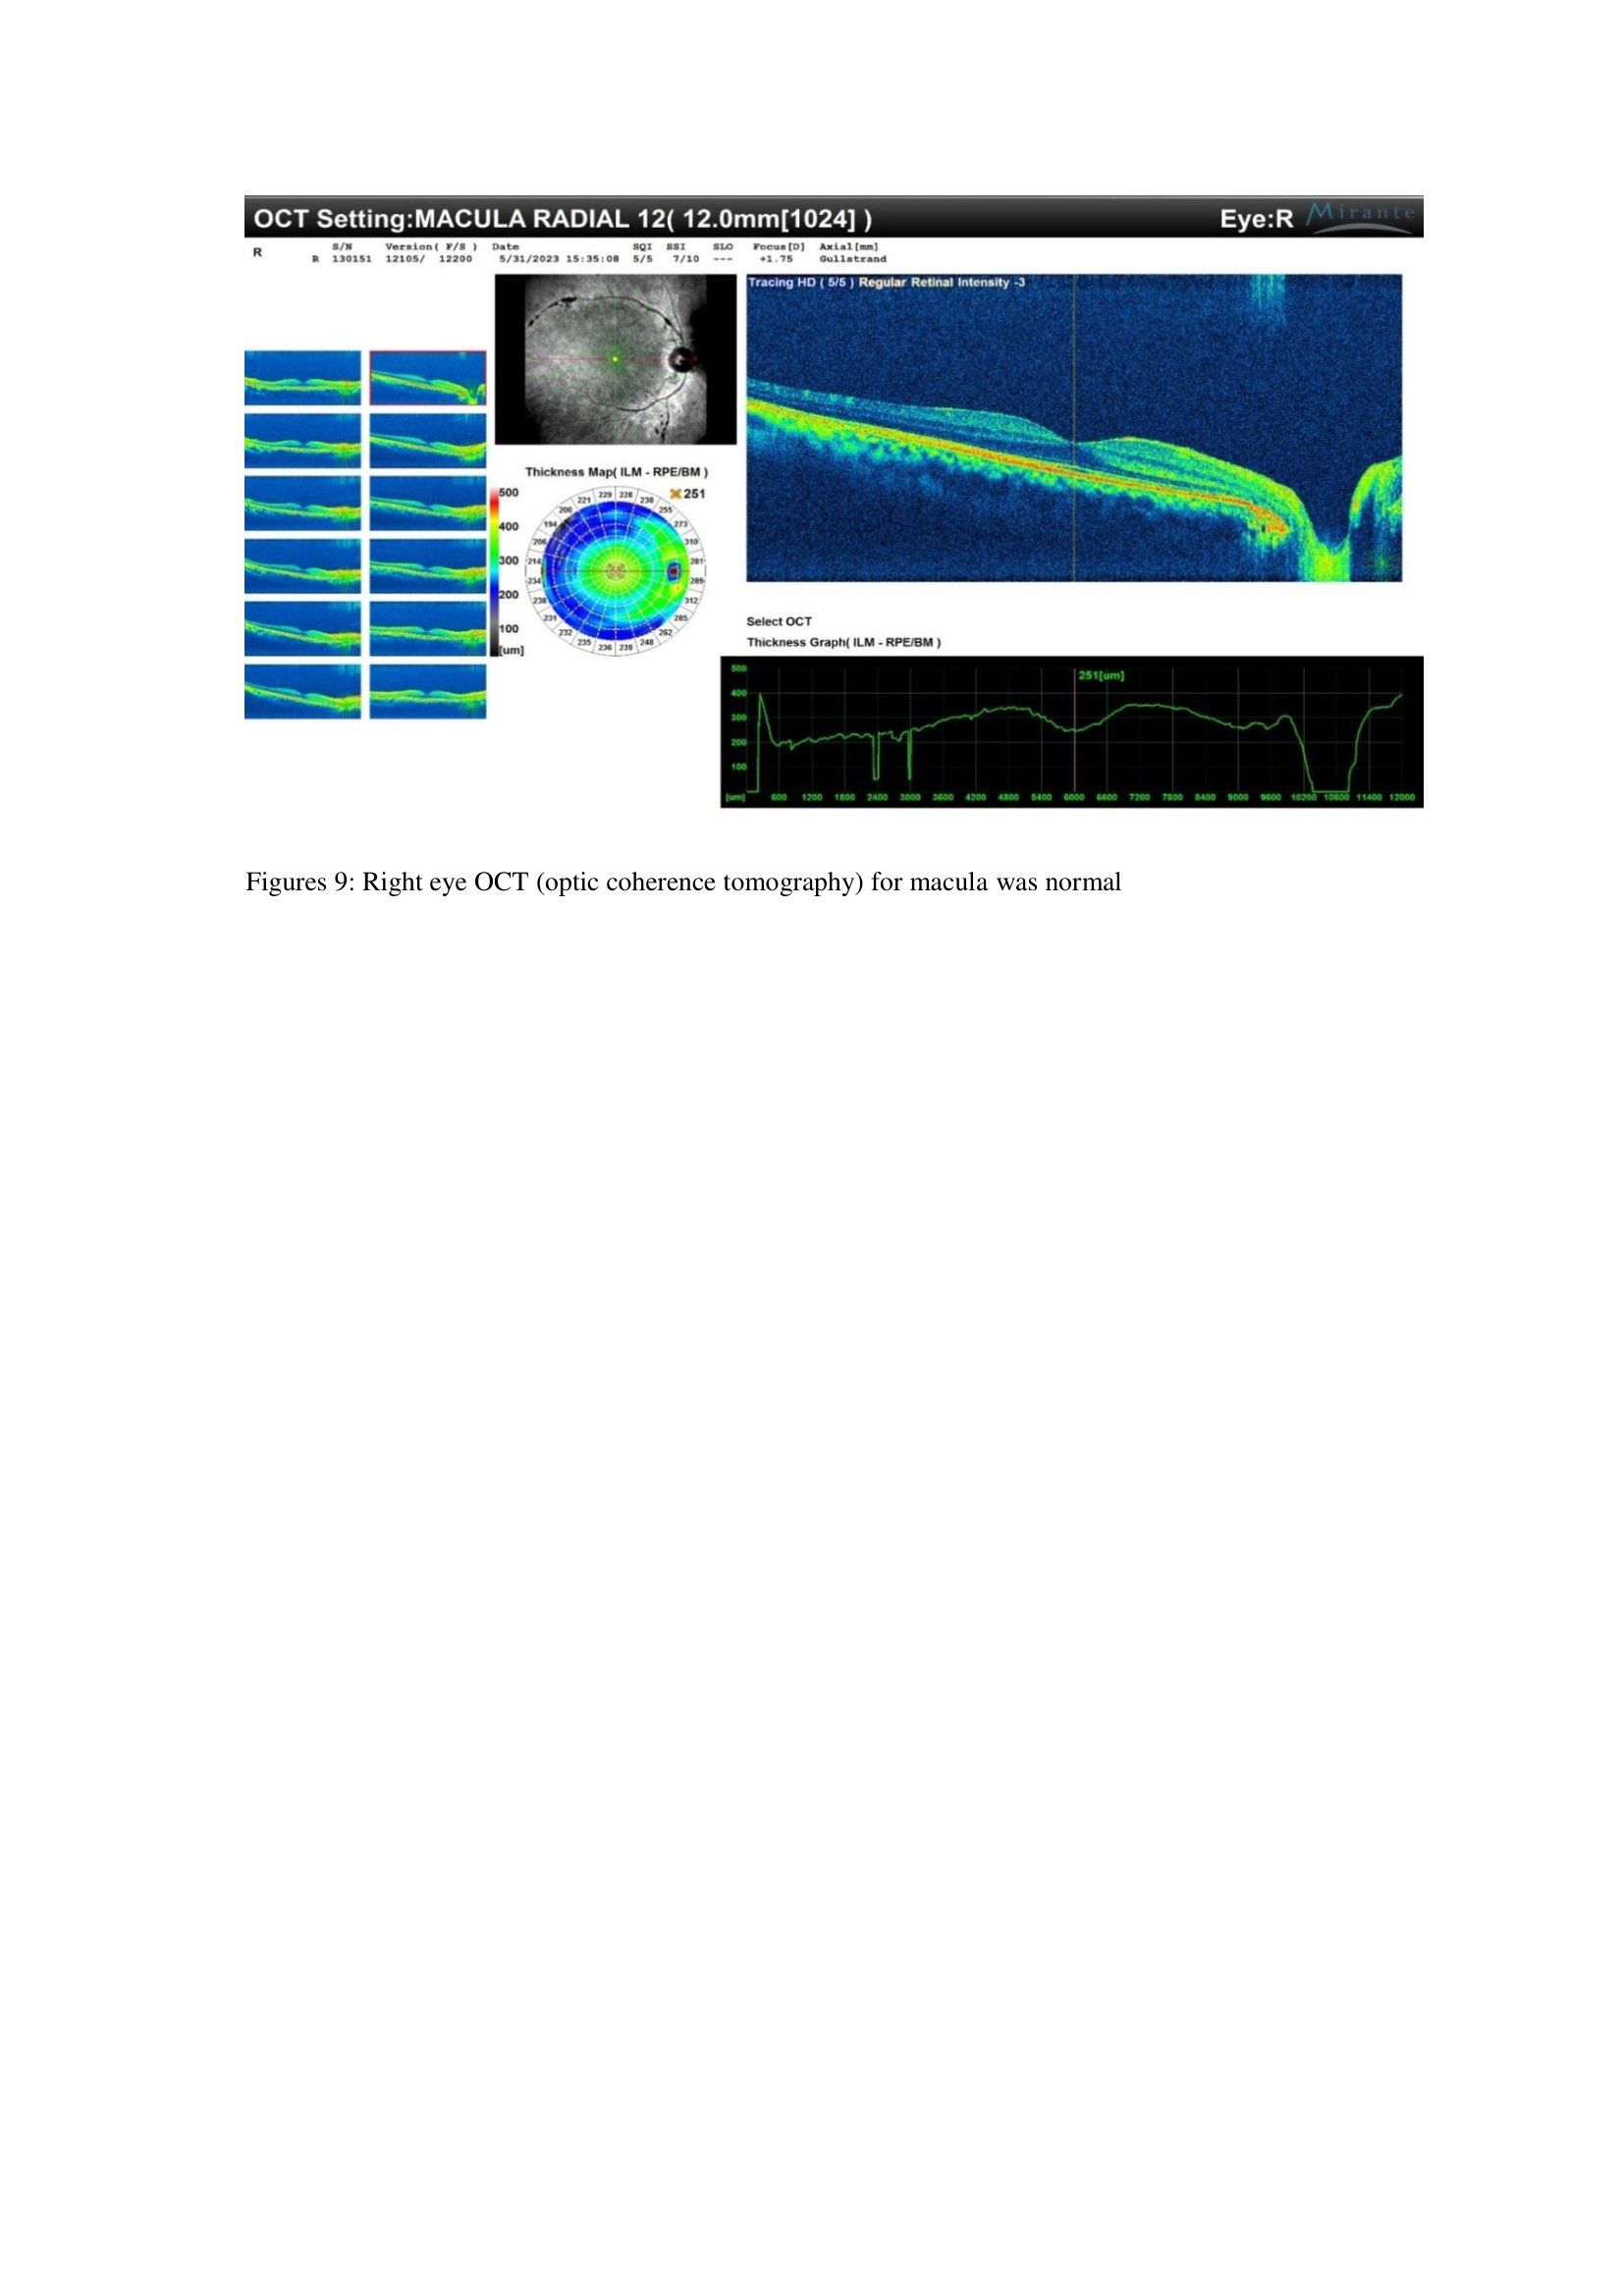

After 12 months, OCT MACULA was done and was normal as shown in figures 9 and 10 below in figures 9 and 10.

Fundus fluorescein angiography during admission showed that there was Central retinal whitening with no cotton wool spots .there was no Obstruction of microcirculatory blood flow with normal perfusion of retinal blood flow, as shown in (figures 1 and 2) for the right eye and (figures 3 and 4) for the left eye.

Fundus fluorescein angiography was done at 12 months, and showed the same malaria pigments along the blood vessels, but there was improvement of macular whitening with complete resolution. The patient retina photos at that visit at 12months are shown in figures 5, 6, 7 and 8) respectively.